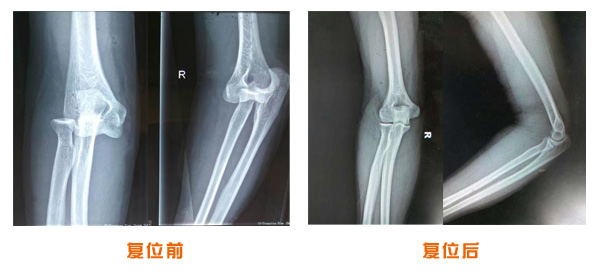

肥城市安駕莊梁氏骨科醫院是一所以梁氏手法正骨配合膏藥為特色的現代化專科醫院。

梁氏骨科術始創于清雍正年間,歷經八代,至今已有三百年歷史。據1929年泰安縣志載“梁瑞圖先生,字增生,號蓮峰,安駕莊人,精岐黃并發(fā)明接骨,凡跌打車凡跌打車軋皮不破而碎骨者......【詳細】 |